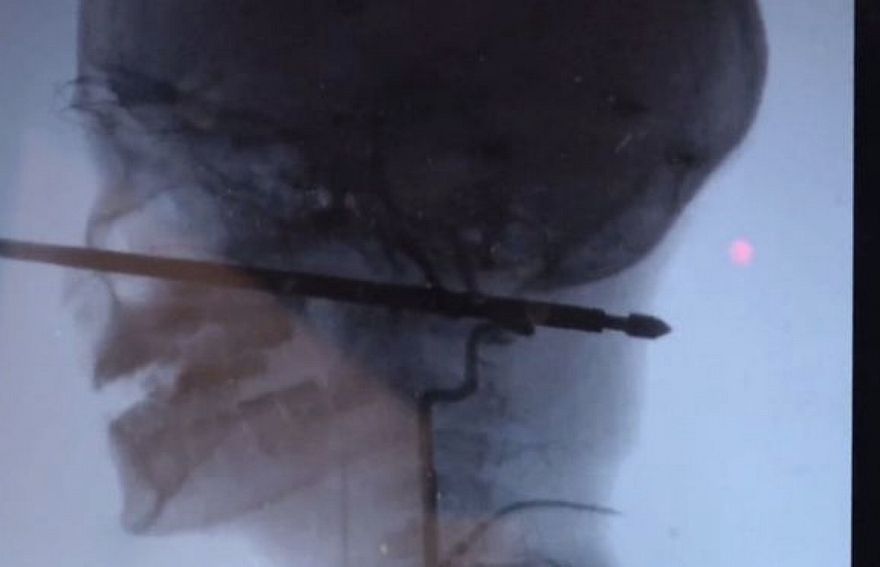

ކުއްޖާގެ މޫނަށް ހެރުނު އޫ ބޮލުން ނުކުމެފައިވާ އިރު ލޮލާއި ސިކުނޑި އަދި މައިބަދަ ވަނީ ސަލާމަތްވެފައި. --ފޮޓޯ:ސީބީއެސް

މިސޫރީ (ސެޕްޓެމްބަރު 13) - މިއީ މިލިއަނަކުން އެކަކު ވެސް ސަލާމަތް ނުވާވަރުގެ ނުރައްކާތެރި ހާދިސާ އެކެވެ. ޓްރީ ހައުސްއަކުން ވެއްޓުނު 10 އަހަރުގެ ކުއްޖެއްގެ މޫނަށް މަސް ފިހަން ގެންގުޅޭ ކަހަލަ އުލެއް ހެރި އެ ކުއްޖާގެ ބޮލުން ހުރީ ނުކުމެފަ އެވެ.

އެމެރިކާގެ މިސޫރީގައި 10 އަހަރުގެ ޒާވިއާ ކަނިންގަމް އުޅުނީ ޓްރީ ހައުސްއެއްގައި ކުޅޭށެވެ. ކުއްލިއަކަށް އޭނާގެ މުޅި ގައިގައި ކުޅަނދުރު ހަފައިގަތުމުން ޓްރީ ހައުސް އިން ވެއްޓި ޖެހުނީ އެއް ފޫޓްގެ ދަގަނޑު އުލެއްގެ މައްޗަށެވެ. ލޯ ކައިރިން ހެރުނު އޫ ހުރީ ބޮލުގެ ނާށިގަނޑު ފަޅާލާފައި އަނެއް ކޮޅަށް ނުކުމެފަ އެވެ. އެކަމަކު އެ އެ ކުއްޖާގެ ލޮލާއި ސިކުނޑި، މައިބަދަ އަދި ލޭނާރުތަކަށް އެއްވެސް ގެއްލުމެއް ނުލިބެ ސަލާމަތްވުމަކީ ބޮޑު މުއުޖިޒާތެއް ފަދަ ކަމެކެވެ. ކެންސަސް ޔުނިވާސިޓީ ހޮސްޕިޓަލްގައި މިހާރު ފަރުވާ ދެމުން އަންނަ އެ ކުއްޖާގެ ހާލު އަންނަނީ ރަނގަޅުވަމުންނެވެ.

ޒާވިއާގެ ބޮލަށް އޫ ހެރުނު ނަމަވެސް ލޭ އައިސްފައެއް ނުވެ އެވެ. ކެންސަސް ޔުނިވާސިޓީ ހޮސްޕިޓަލްގެ އެންޑޯވެސްކިއުލާ ނިއުރޯސާޖަރީ ޑިރެކްޓަރު ކޯޖީ އެބާސޯލް ވިދާޅުވީ ބޮލުގެ އެއްކޮޅުން އަނެއްކޮޅަށް ހަ އިންޗި އަށް އުލެއް ވަދެ ފޫގޮސްފައިވާ އިރު ލޮލާއި ސިކުނޑި، މައިބަދަ އަދި ލޭހޮޅިތައް ސަލާމަތްވުމަކީ މިލިއަނަކުން އެކަކަށް ވެސް ދިމާ ނުވާވަރުގެ ނުރައްކާތެރި ހާދިސާއެއް ކަމަށެވެ. އެ ކުއްޖާ ސަލާމަތްވުމަކީ ބޮޑު މުއުޖިޒާތެއް ކަމަށް ޑޮކްޓަރު ވިދާޅުވި އެވެ.